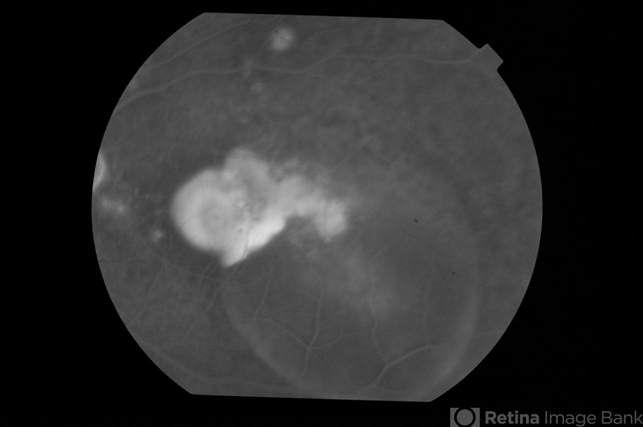

- Bilateral chronic central serous chorioretinopathy

- central serous chorioretinopathy (CSCR), bilateral chronic central serous retinopathy

- Late phase fluorescein angiogram of left eye of a 33-year-old gentleman with bilateral CSC.